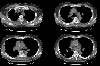

Computed tomography again demonstrated patchy, bilateral, peripheral, non-segmental regions of consolidation which were sharply demarcated from adjacent normal lung. Cavitation was suggested in some regions of consolidation. Some of the opacities appeared streaky or band-like. Areas of ground glass opacification were also seen. Interlobular interstitial thickening and intralobular reticular opacities were noted in association with the areas of consolidation. Mediastinal adenopathy was identified and has been described in patients with chronic eosinophilic pneumonia. The appearance of CEP on computed tomography may be indistinguishable from bronchiolitis obliterans and organizing pneumonia (BOOP). Following institution of steroid treatment, the consolidations may begin to clear in as soon as two weeks- typically from the periphery.

Lung windows:

Soft tissue windows: